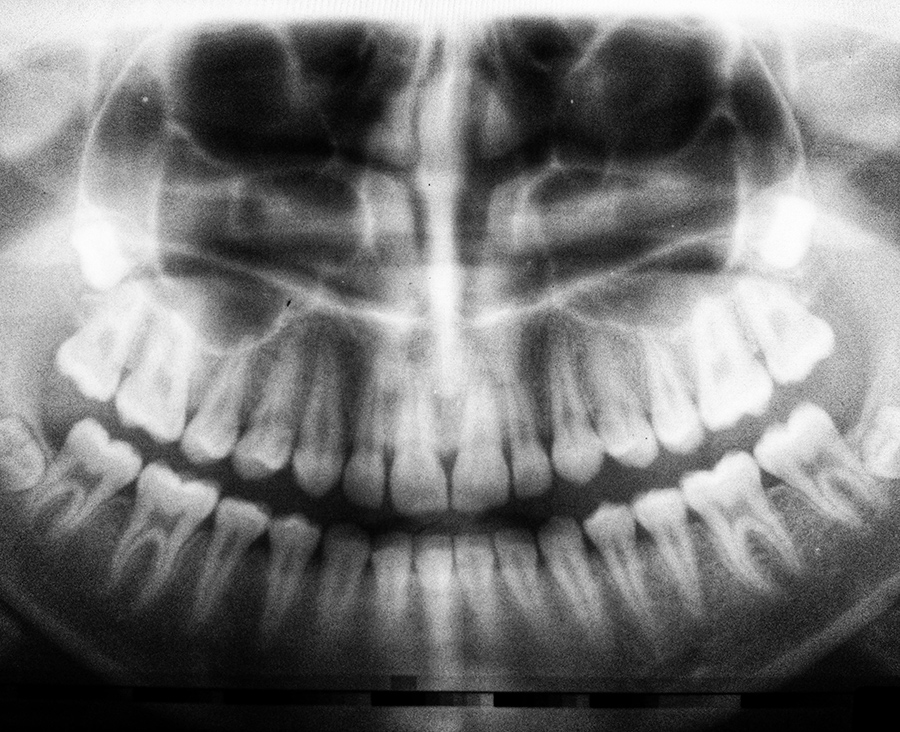

radiologie

La Smile Dent Clinics radiologia este un serviciu in-house.

Ne gândim mereu la experiența pacienților noștri. Am adus, deci, și serviciul radiologiei la noi în clinică pentru a evita disconfortul drumurilor suplimentare la alte clinici și pentru a controla la nivel de impecabil tot lanțul de tratament.

Cu serviciul de radiologie în aceeași locație, precizia intervențiilor este inegalabilă, iar posibilitățile de inovare a tratamentului sunt nesfârșite. Imaginează-ți o intervenție chirurgicală de mare finețe, în care, după primul pas al montajului, pacientul merge în camera de radiografie, iar doctorul primește la nivel de minut o radiografie 3D ce include deja intervenția proaspăt făcută.

Rezultatul este precizie absolută în toate celelalte ramuri ale clinicii: de la Chirurgie la Ortodonție și de la Implantologie la Profilaxie.